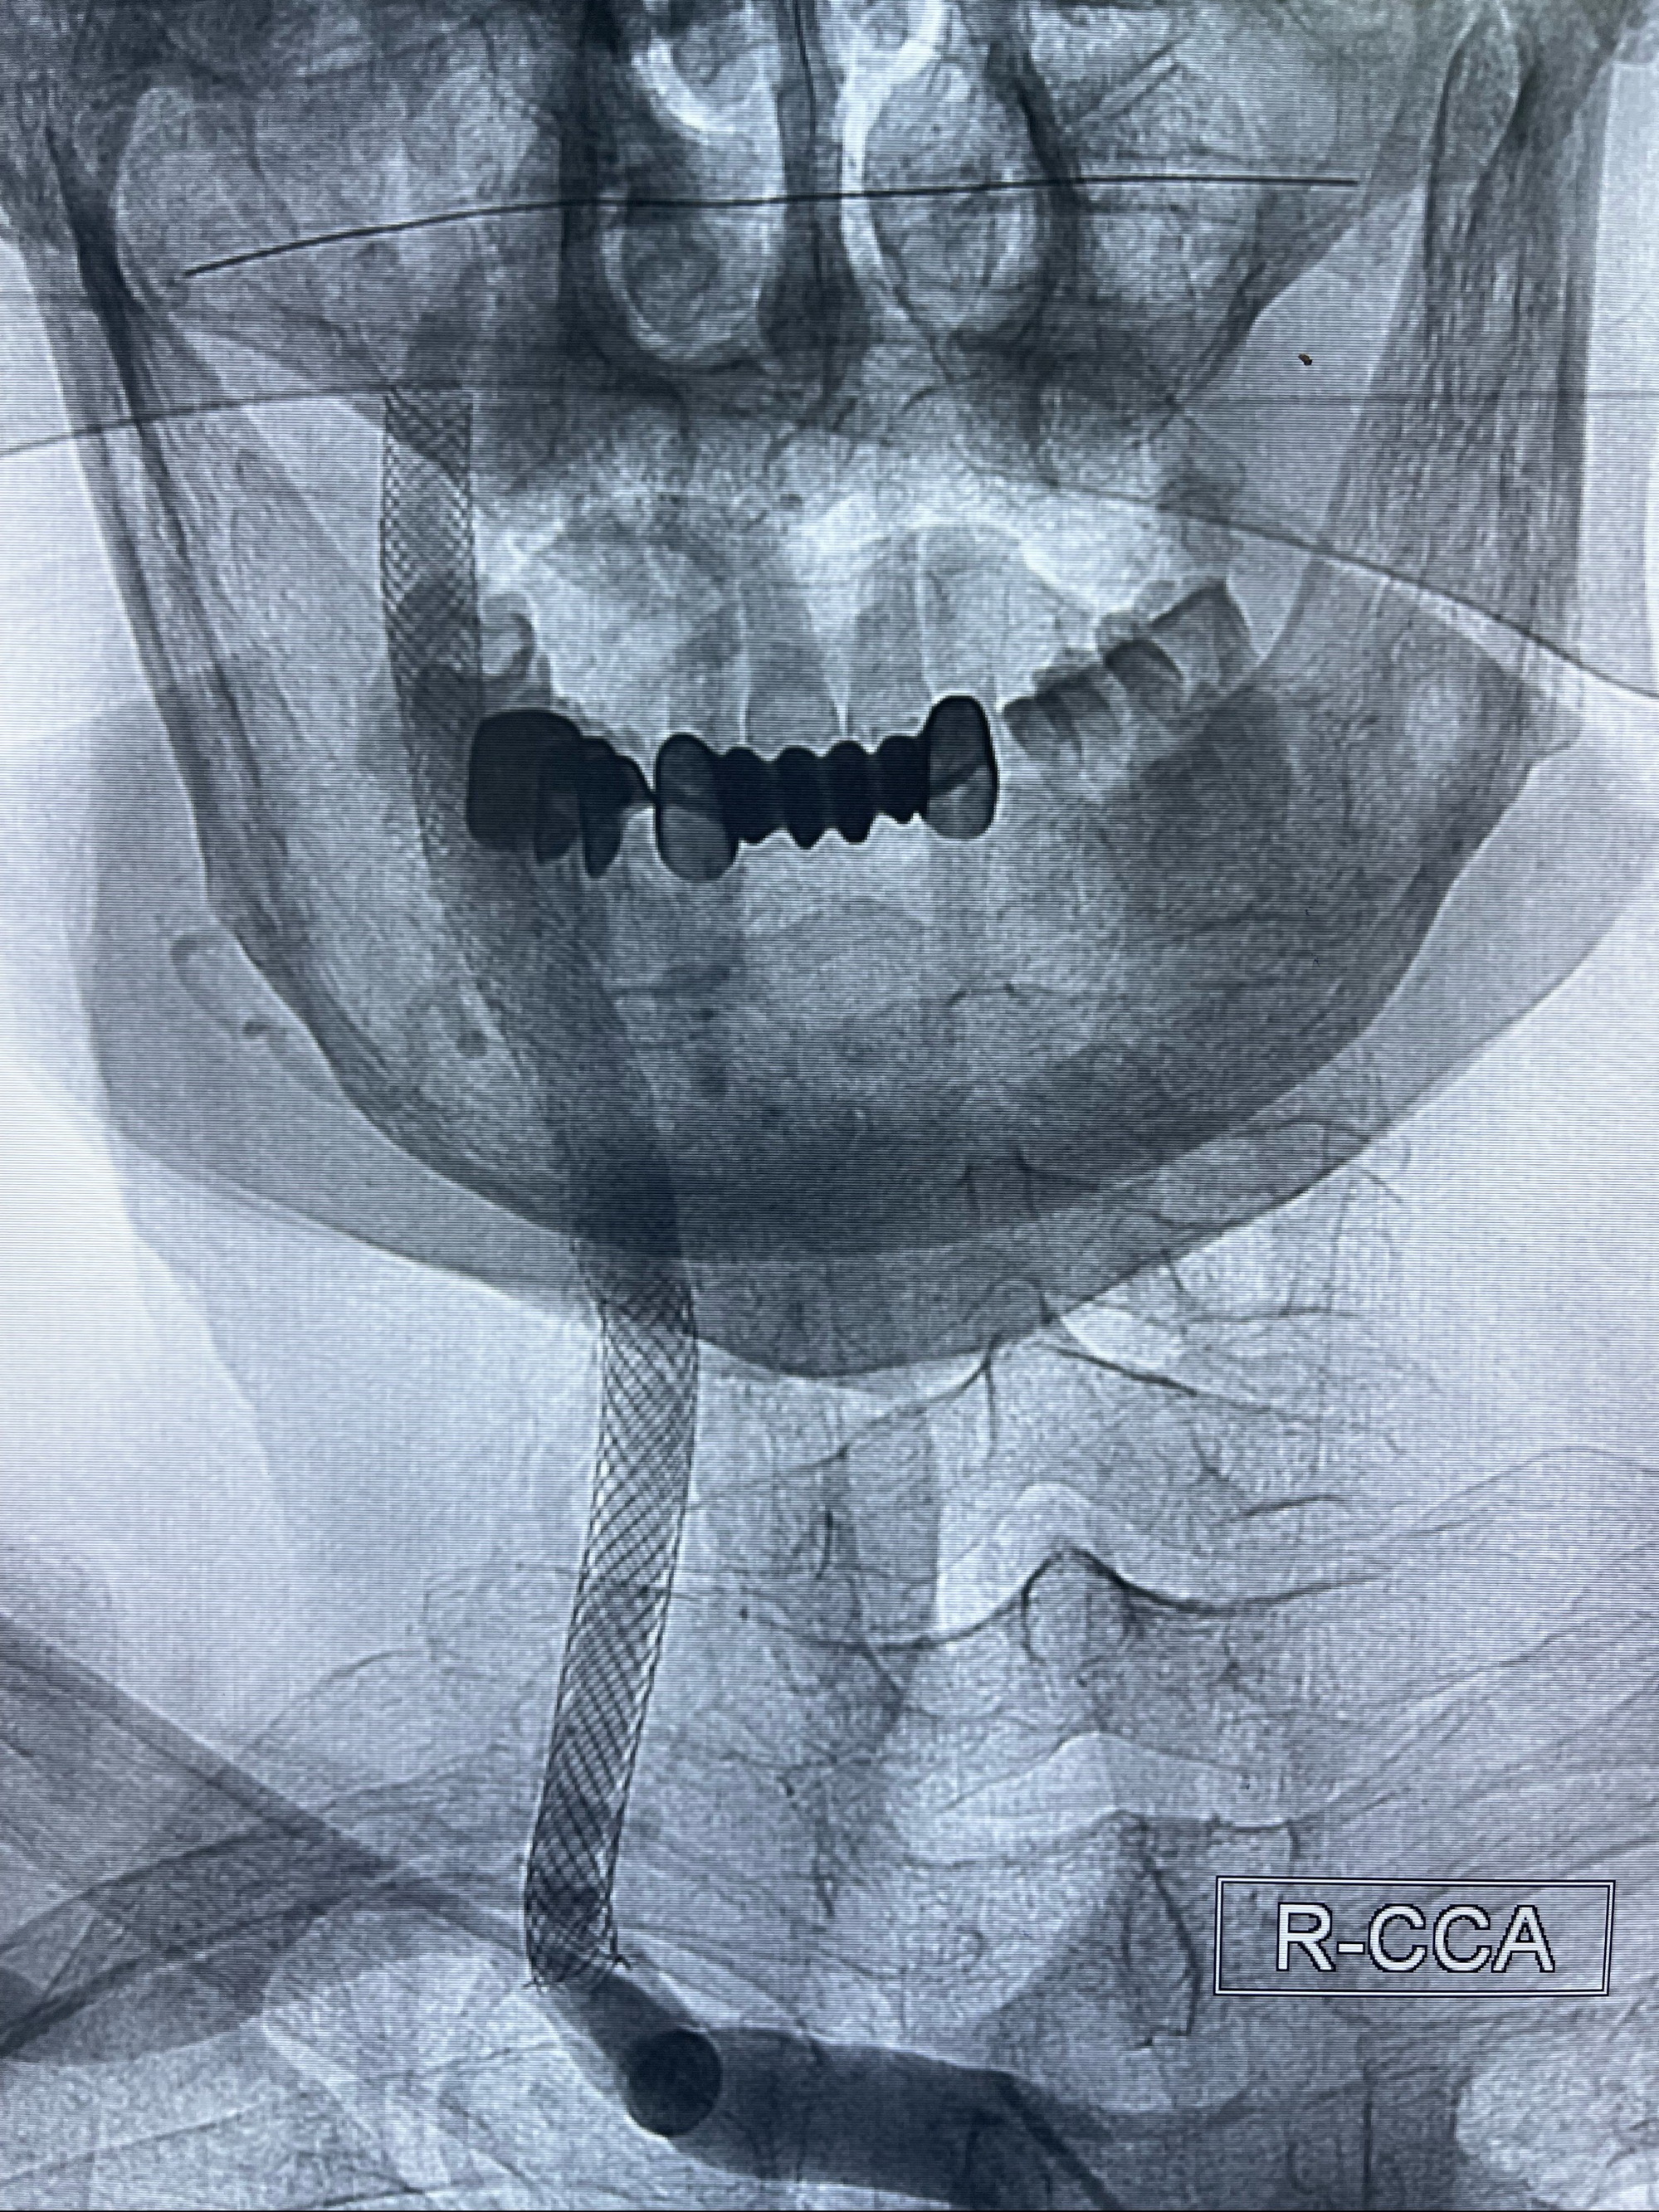

088NeuroMAX100cm长鞘在125cmMPA及黑泥鳅导丝引导下超选择性插入右侧颈内动脉支架内

经导引导管造影显示支架远端颈内动脉不规则狭窄伴局部充盈缺损,同时行全身肝素化5ml